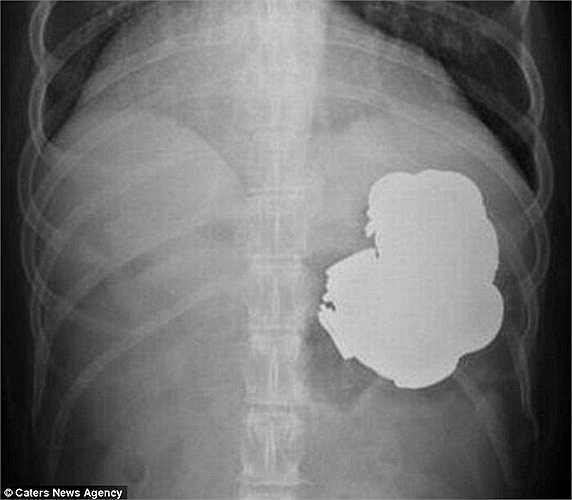

Tuy nhiên, sau khi tiến hành chụp X-Quang các bác sỹ thấy một khối dị vật nằm trong dạ dày của anh Rajpal.

Các bác sỹ phải tiến hành 240 lần nội soi và một ca phẫu thuật dài 9 tiếng để lấy 140 đồng xu, 150 chiếc đinh tán cùng vô số ốc vít, bu-lông, và cả những cục pin.